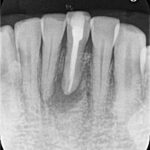

初診来院時の状態では、すでに根の入り口付近に処置が行われている状態でした。患者様によると、腫れた時に少しだけ歯を削ったとのことでしたが、どのような処置が行われていたかは説明を受けていなかったとのことです。

根の先に黒い影(膿・骨の吸収)が認められ、神経の検査では反応がなく、神経が死んでしまっている状態でした。